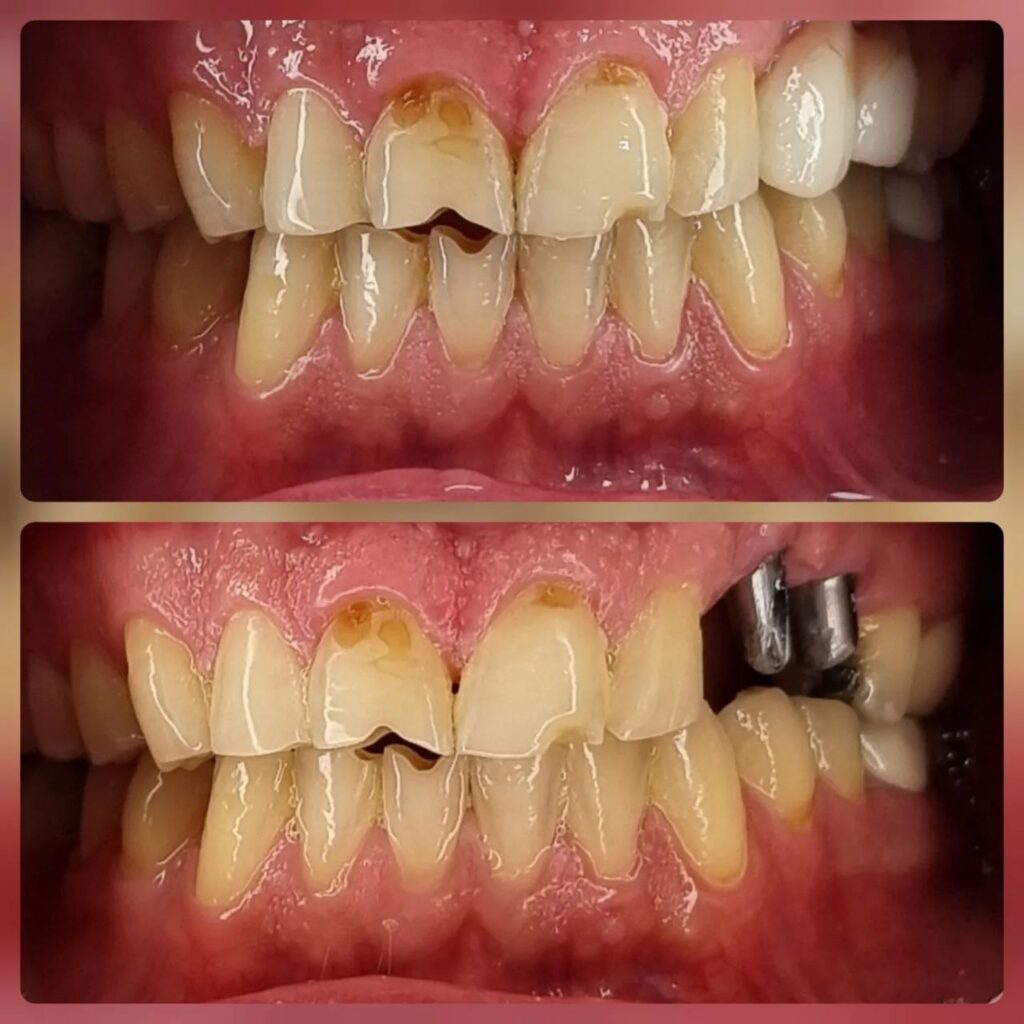

کاشت ایمپلنت دندان

اطمینان حاصل کردن از اینکه دندانهایتان به نحوی زیبا و طبیعی جایگزین شدهاند، از اهمیت بسیاری برخوردار است. ایمپلنت دندان به عنوان یک روش درمانی دائمی در دندانپزشکی شناخته میشود که حاصل آن، یک دندان زیبا و طبیعی در دهان شما خواهد بود.

هرچند که این روش درمانی هزینهی بیشتری نسبت به روشهای دیگر دارد، اما ارزش زیبایی که ایجاد میکند، قابل انکار نیست. ایمپلنتها به قدری شبیه به دندانهای طبیعی هستند که به سختی میتوان آنها را از دیگر دندانها تشخیص داد.